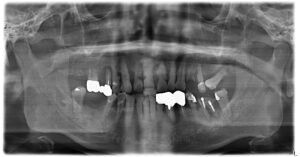

ケース2:上下に多くの問題があった70代後半男性

この方は虫歯や歯周病で残存歯が少なく、グラグラの歯が多い状態でした。最初は保険のクラスプ義歯を入れていたものの安定せず、硬いものを噛めないため外していることが多かったそうです。外見を重視してナイロン義歯を試されましたが、期待したような咬合回復は得られず、全体の再治療を希望して来院されました。

まず全顎の虫歯と歯周病の治療を行い、上顎は残存歯すべてに内冠をかぶせて連結し、全体を支えるテレスコープ義歯を製作しました。装着後は「入れ歯」というよりは取り外し可能な長いブリッジの感覚で、違和感がほとんどないとのことです。

このケースは「残った歯をチーム化して守る」発想が有効であった例です。